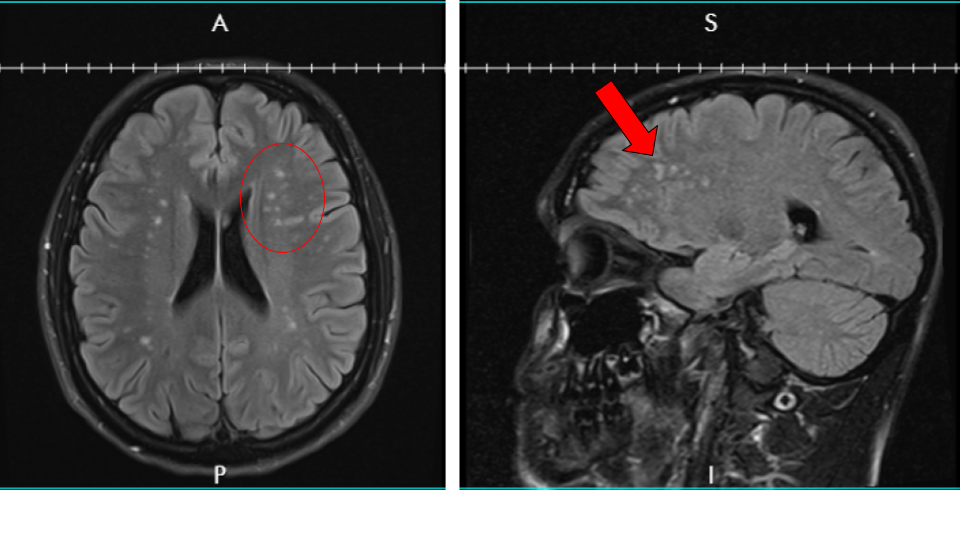

After weeks of trying to get an appointment, I finally saw the doctor and he ordered a bunch of tests including an EEG and an MRI. The EEG was normal. The MRI was not. The MRI revealed that I had lesions on my brain. A lot of them. I had more tests after that including a spinal tap to check for MS but nothing that revealed anything specific. The neuro gave up and said he couldn’t help me so I found a couple more, which took months to schedule.

Finally, in October, it looks like we may have finally found the answer to my symptoms. A genetic test revealed a mutation to the COL4A1 gene which produces collagen in the brain. In other words, due to a genetic mutation, my small blood vessels (especially in the brain) are fragile and can break easily. Which means certain areas of my brain weren’t getting enough blood and the cells died, which is what the white spots on the MRI showed and why I had the symptoms I was experiencing. There is no cure, and it’s something that I’m going to have to treat and monitor for the rest of my life.